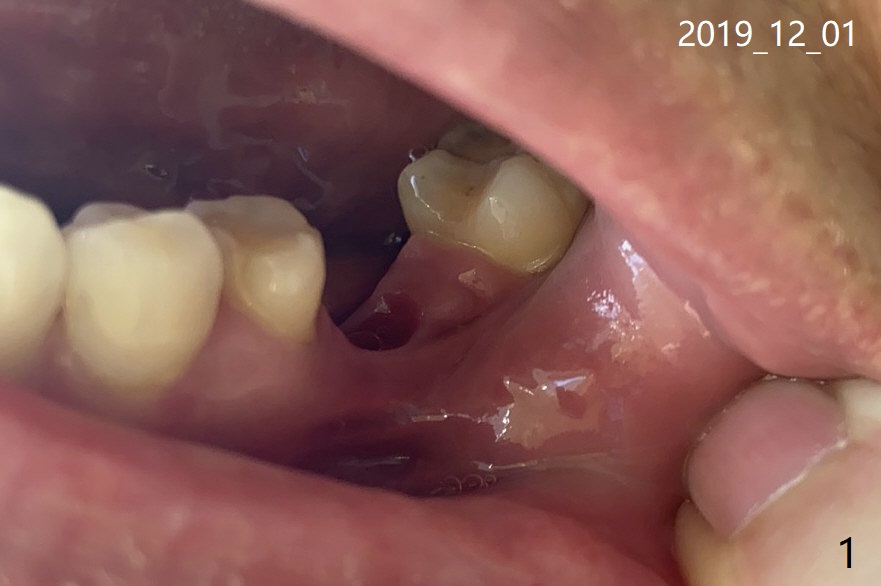

I just forward my wife's email to you.  Unfortunately her planted tooth got off from the foundation (Fig.1,2 (7 months post cementation)).  We have visited several clinics in Beijing.  They do not have the tool to handle it because the model you used is not popular in Beijing.  Would you like to lend your tool to us? We will send it to you once repair is done.  December 1, 2019, 07:37:14 AM EST

I am so sorry to hear your misfortune. Most doctors do not like to take over a case of somebody else. The problem may not be so difficult to solve. It is the best to see a private dentist with experience in implant. The instrument to be used to tighten the crown/abutment is the most popular (universal) in the world. It is called 1.2 driver. We do not mind sending you one, but it takes time. It would be the best to place the crown/abutment as soon as possible. Ask the doctor to open up a hole in the middle of the crown, try to use his/her most often used driver to match the screw, tighten the screw at 30 Ncm and retighten it at 35 Ncm in 10 minutes or in a few days. Finally adjust occlusion. I am afraid that I had written down the procedure before your wife left my office.  Dec 1 at 9:43 AM

The final abutment used in my office is called Cemented abutment: 6.5x5.5(5) mm. 6.5 diameter, 5.5 mm abutment length, 5 mm cuff length or height.   Since the tooth had been lost for long time, your bone loss was severe. The abutment screw has higher chance of being loosened.

If the dentist cannot place the cemented abutment temporarily, use a healing abutment, smaller in diameter, but length longer first. For example, 5x6 mm. Gradually use the one with larger diameter.